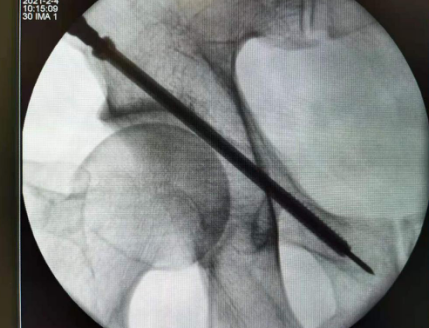

准确置入螺钉

术中,在天玑骨科机器人导航下置入固定右耻骨上支导针,透视见导针位置长短适中,螺钉固定,手术切口不到1公分,手术很顺利,约1小时完成。术后,患者恢复良好,目前已出院。